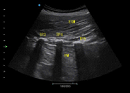

MFI:Mediante la reducción de la distorsión de la señal y la eliminación de ruidos no deseados, la MFI ofrece imágenes de alta calidad con una excelente resolución alto contraste y mayor penetración.

Xbeam:La tecnología ayuda a aliviar los artefactos de eco y mejorar la resolución espacial.

Nanoview:Mediante la reducción de ruidos y artefactos Nanoview es capaz de presentar pequeñas lesiones al suavizar las imágenes con distintos tejidos y mejorar el borde ayudando a ofrecer resultados de diagnóstico confiable.

Fusión THI:Fusionando la información de diferentes bandas de frecuencia en tiempo real la Fusion THI implementa la transmisión de banda ancha y la recepción de ondas armónicas.